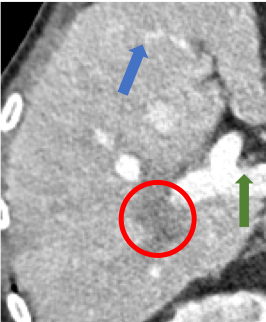

Indeed, the images of WGAN-VGG[37], as shown in Fig. 3j, exhibit better visual quality with respect to more details and share structural details similar to NDCT images according to human perceptual evaluations. However, Figs. 4j (marked by the red circle) and 6j (marked by the green circle) suggest that it may severely distort the original structural information. A possible reason is that the VGG network [47] is a pre-trained deep CNN network based on natural images, and the structural information and contents of natural images are different from medical images.

Compared with WGAN and WGAN-VGG, our proposed SMGAN-3D, as shown in Figs. 4l (marked by the red circle) and 6l (marked by the green circle), can more clearly visualize the metastasis and better preserve of the portal vein.

To validate the robustness of DL-based methods, we compared our method with the image space denoising method. Figs. 4h and 6h show that BM3D blurs the low-contrast lesion marked by the red circle and smooths specific features marked by the blue arrow. In contrast, SMGAN-3D exhibits better on the low-contrast lesion and yields sharper features as shown in Figs. 4l and 6l.